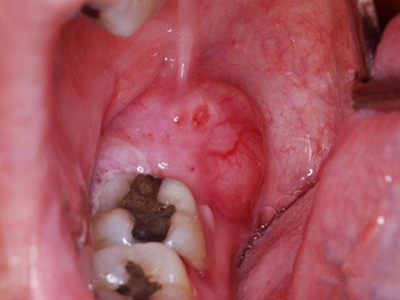

阻生牙是指由于邻牙、骨或软组织的阻碍而只能部分萌出或完全不能萌出,且以后也不能萌出的牙。引起牙阻生的成因,主要是由于颌骨缺乏足够的空间容纳全部恒牙。常见的阻生牙为下颌第三磨牙、上颌第三磨牙及上颌尖牙。

阻生牙可反复引起冠周炎,或引起邻牙牙根吸收和破坏,位置不正,不能完全萌出,好发部位是上、下颌第三磨牙。